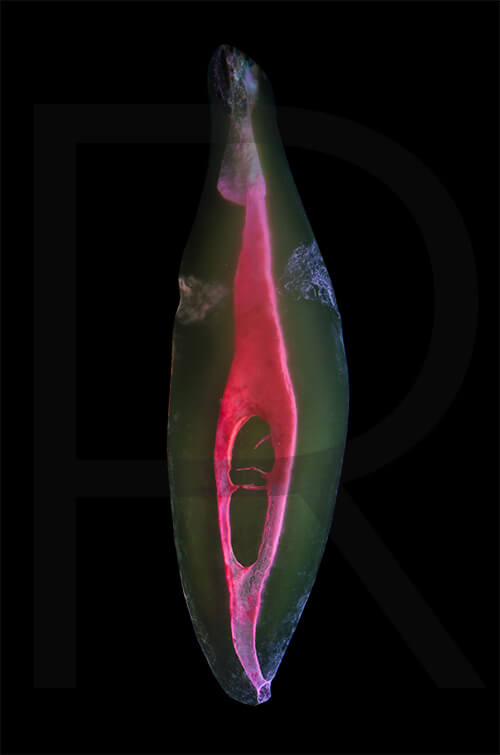

Bildauswahl mit schwebender Aufhängung

- Foto hinter 3mm Acrylglas, rahmenlos

- hochwertige, unsichtbare Aufhängung, "schwebend“

- Hoher UV-Schutz für lang anhaltend strahlende Farben

- Bruchsicher und leichter als Glas

- Beeindruckende Farben und brilliante Tiefenwirkung

- Druck erfolgt ohne Wasserzeichen

- Bildgröße Bild 7: 90 x 90 cm, quadratisch

- Preis: auf Anfrage, zuzüglich 20,90 Euro Versand & Porto innerhalb Deutschlands, weiterer Versand auf Anfrage

- Bildgröße Bild 8: 90 x 60 cm, Hochformat

-

Preis: 490,00 Euro, zuzüglich 16,90 Euro Versand & Porto innerhalb Deutschlands, weiterer Versand auf Anfrage

Wenn Sie Interesse an den Fotos transparenter Zahnpräparate haben, bieten wir hier die Möglichkeit einige Versionen als Acrylbilder (alle Detailinformationen zu Größe und Preis siehe obige Auswahl) zu bestellen.

Die Bilder sind nicht nur zur Praxisverschönerung geeignet sondern auch eine wertvolle Unterstützung bei der Patientenberatung vor endodontischen Behandlungen.